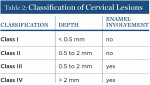

The authors have devised and published a classification of cervical lesions based on the depth of the cervical lesion and whether or not there is enamel involvement: 1) Class I, shallow depth (< 0.5 mm); 2) Class II, moderate depth (0.5 mm to 2.0 mm) with no enamel involvement; 3) Class III, moderate depth (0.5 mm to 2.0 mm) with enamel involvement; and 4) Class IV, deep (greater than 2.0 mm depth) with enamel involvement (Table 2).1